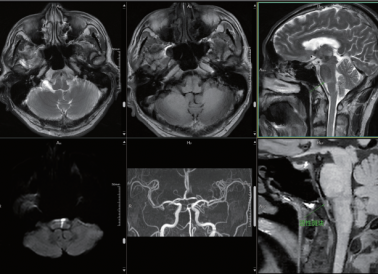

原理先容:3D-TOF-MRA是一种无创性的血管检查手艺,使用 MRI 成像手艺来描绘剖解组织中血管路径并三维展示出来的要领,对动脉特殊敏感,无需注入比照剂, 可使血管显影

临床用途:MRA能直接显示动脉瘤巨细、部位、形状,能多方位多角度视察瘤体整体情形,3D-TOF-MRA靶血管重组的要领针对重点部位举行剖析,提高动脉瘤&小动脉瘤诊断的准确性